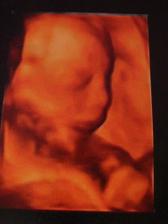

Náš drobeček...

focení v 33t.tt :-